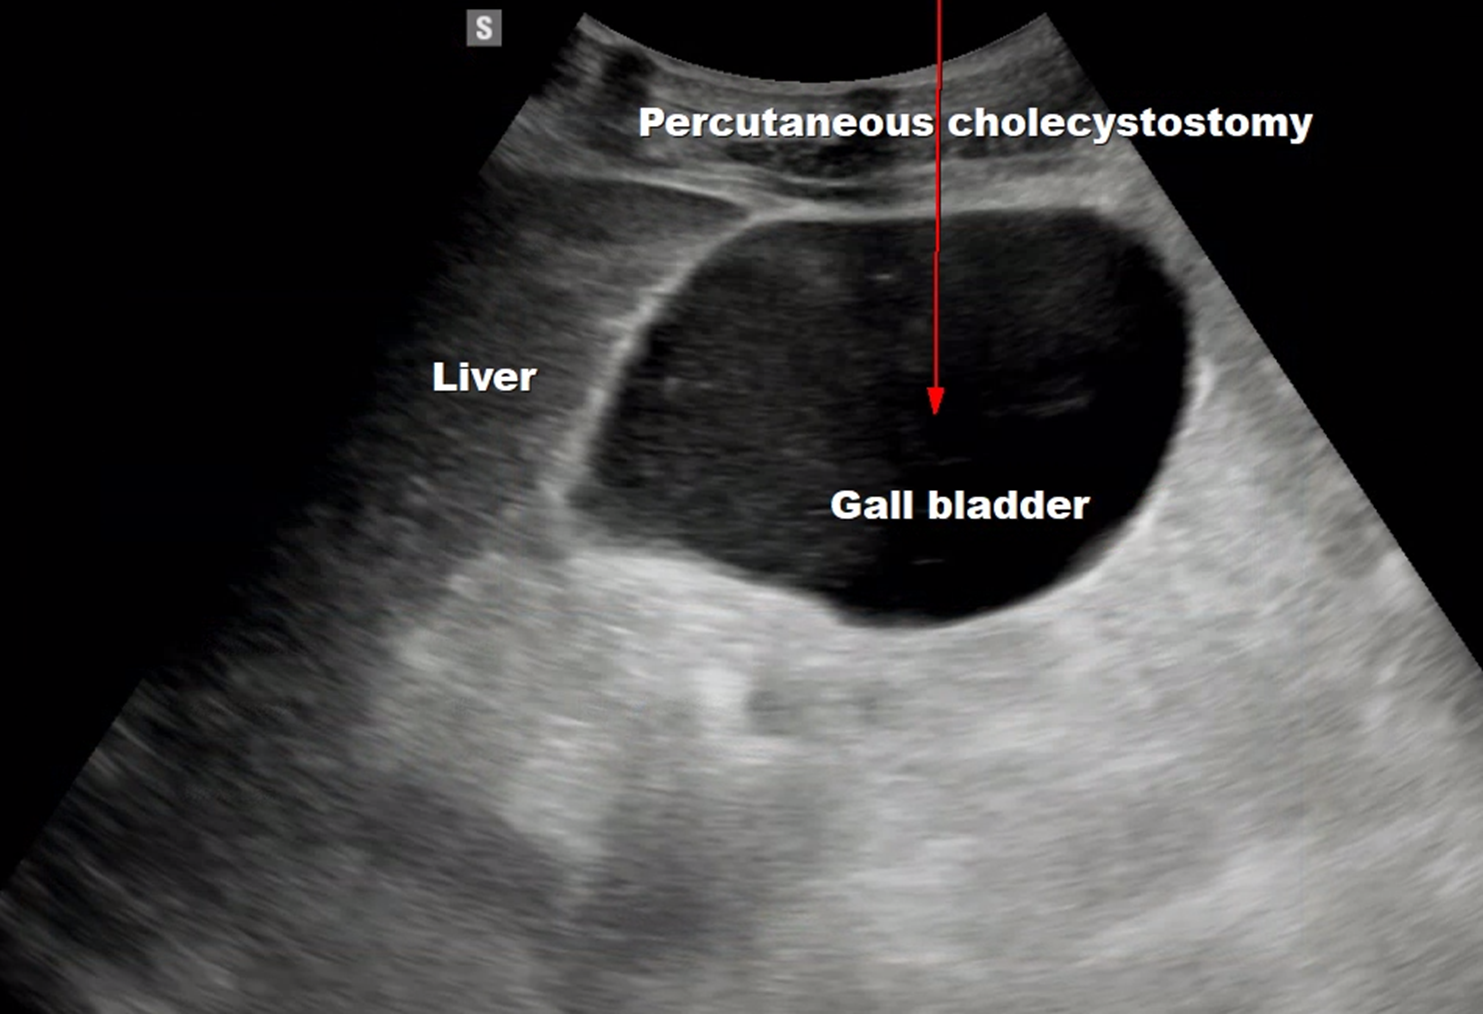

시술을 준비하며, 초음파로 먼저 담낭을 확인합니다.

그리고 정말 급성 담낭염이 맞는지 한 번 더 확인을 합니다.

이렇게, 정말 급성 담낭염이라는 것이 확인이 되면 들어갈 경로를 결정합니다.

바늘과 배액관이 진입할 경로에 다른 장애물이 있는 지, 안전한 시술이 가능할 지 확인하는 작업이죠.

그 다음 배액관이 들어갈 자리에 소독을 하고, 초음파로 늘어난 담낭을 보고 이를 바늘로 찌릅니다.

바늘로 담낭이 잘 찔려졌는지 엑스레이 장비로 실시간으로 확인한 뒤, 배액관을 삽입합니다.

왼손으로는 초음파를 보면서, 오른손으로는 바늘을 들고 담낭을 천자합니다.